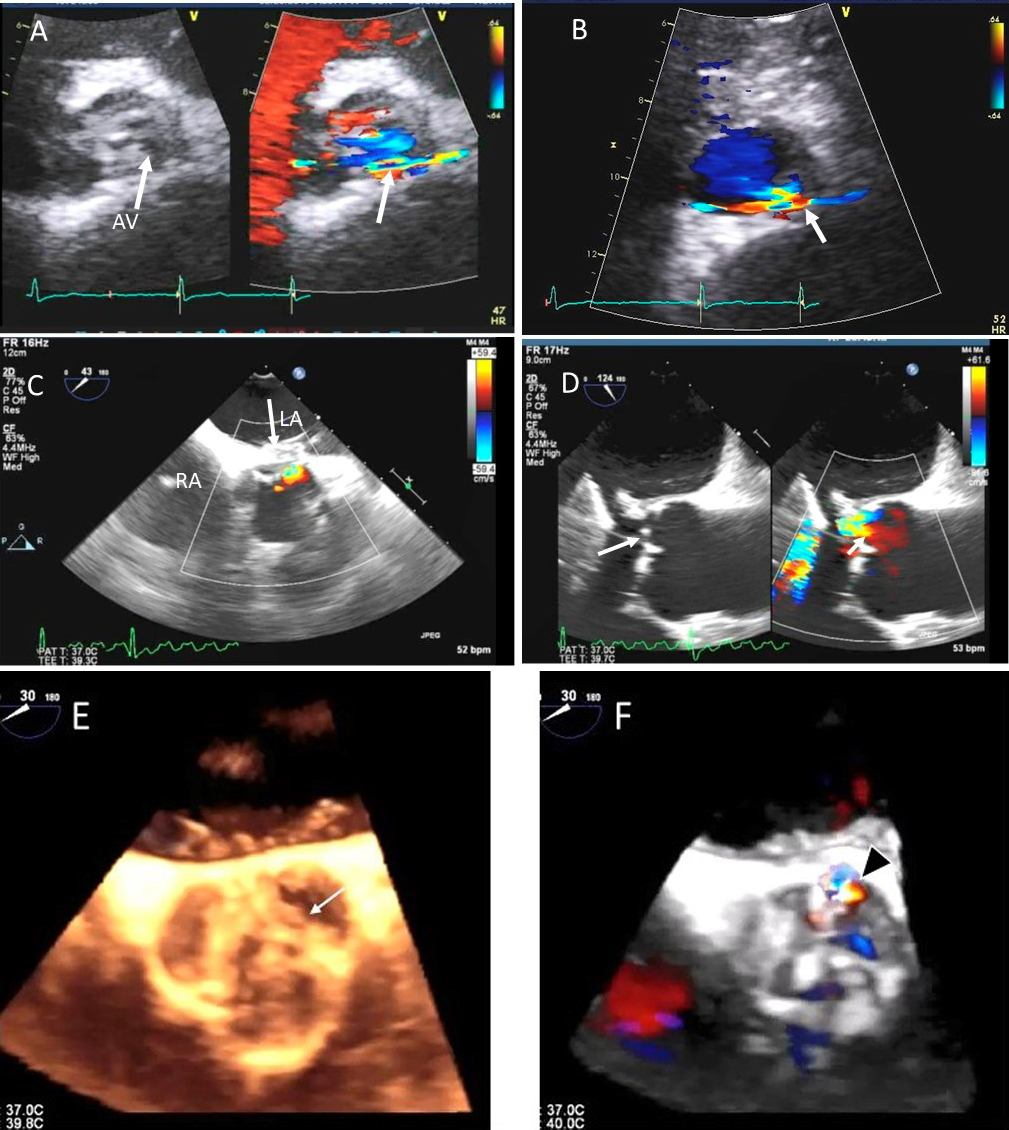

II Aortic cusp prolapse/perforation: endocarditis, aortic dissection (Figs. 8, 9)

Fig. 8.Aortic regurgitation and left coronary cusp perforation. (A) TTE color Doppler parasternal short axis view demonstrating left coronary cusp perforation (white arrows), resulting in aortic regurgitation. (B) TTE color Doppler short axis view showing origin of aortic regurgitation through the left coronary cusp perforation (white arrow). (C) TEE color Doppler short axis view showing a better delineation of the origin of aortic regurgitation jet through the left coronary cusp perforation (white arrow). (D) TEE long axis view demonstrating the perforated coronary cusp on 2D (white arrow) with aortic regurgitation jet originating through the perforation (white arrow) and not through the aortic leaflet coaptation. (E) 3-dimensional (3D) TEE short axis view of the aortic valve showed a clear definition of the left coronary cusp perforation (white arrow). (F) 3-D TEE color Doppler short axis view showing aortic regurgitation jet originating through the left coronary cusp (black arrowhead). Direct planimetry of color Doppler aortic regurgitant orifice can be performed online or via offline post processing of 3D data sets without geometrical assumptions of PISA method or continuity equation.

Common causes of leaflet malfunction causing AR include degenerative leaflet calcifications, and infective endocarditis (Fig. 10), bicuspid aortic valve perforation and rheumatic fever. The causes of AR include Marfan’s syndrome, annulo-aortic ectasia (idiopathic root dilatation) (Fig. 9), aortic dissection, connective tissue disease, and syphilis. The Carpentier classification is also widely used to describe the mechanism of AR [63].

Using 2D biplane, 3D and 3D color Doppler, the exact perpendicular plane to the aortic regurgitation jet can be identified, from which planimetry of the AV coaptation gap as well of the color Doppler vena contracta can be performed [64]. This has been shown to have a good correlation with aortographic grading of AR. When the shape of the regurgitant orifice is nonsymmetric, by using 3D images, invalid geometric assumptions of the vena contracta can be avoided with direct measurement [65]. 3D echocardiographic color Doppler also allows visualization, and measurement of multiple jets and correlated morphologically with surgical findings [65].

Isolated aortic valve perforation can occur post endocarditis or post cardiac surgery [15, 16, 17]. Restriction of aortic valve leaflet motion may occur due to leaflet tethering [18, 19]. Combined use of 2D, color Doppler and 3D TEE may facilitate location and mechanism of AR and can allow valve repair instead of replacement.